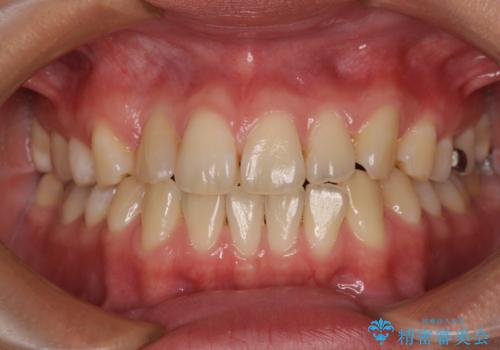

[マウスピース矯正] 海外留学中でも可能な矯正治療

担当医 大元洋佑

![[マウスピース矯正] 海外留学中でも可能な矯正治療の症例 治療前](https://seimitsushinbi.jp/wp/wp-content/uploads/2025/01/C4-1-500x350.jpg?v=1737343006)

![[マウスピース矯正] 海外留学中でも可能な矯正治療の症例 治療後](https://seimitsushinbi.jp/wp/wp-content/uploads/2025/01/IMG_0074-500x350.jpg?v=1737343049)